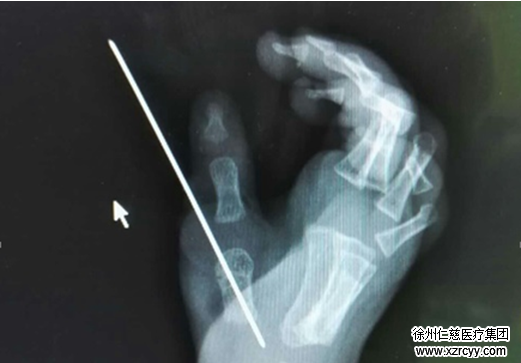

术后x光片